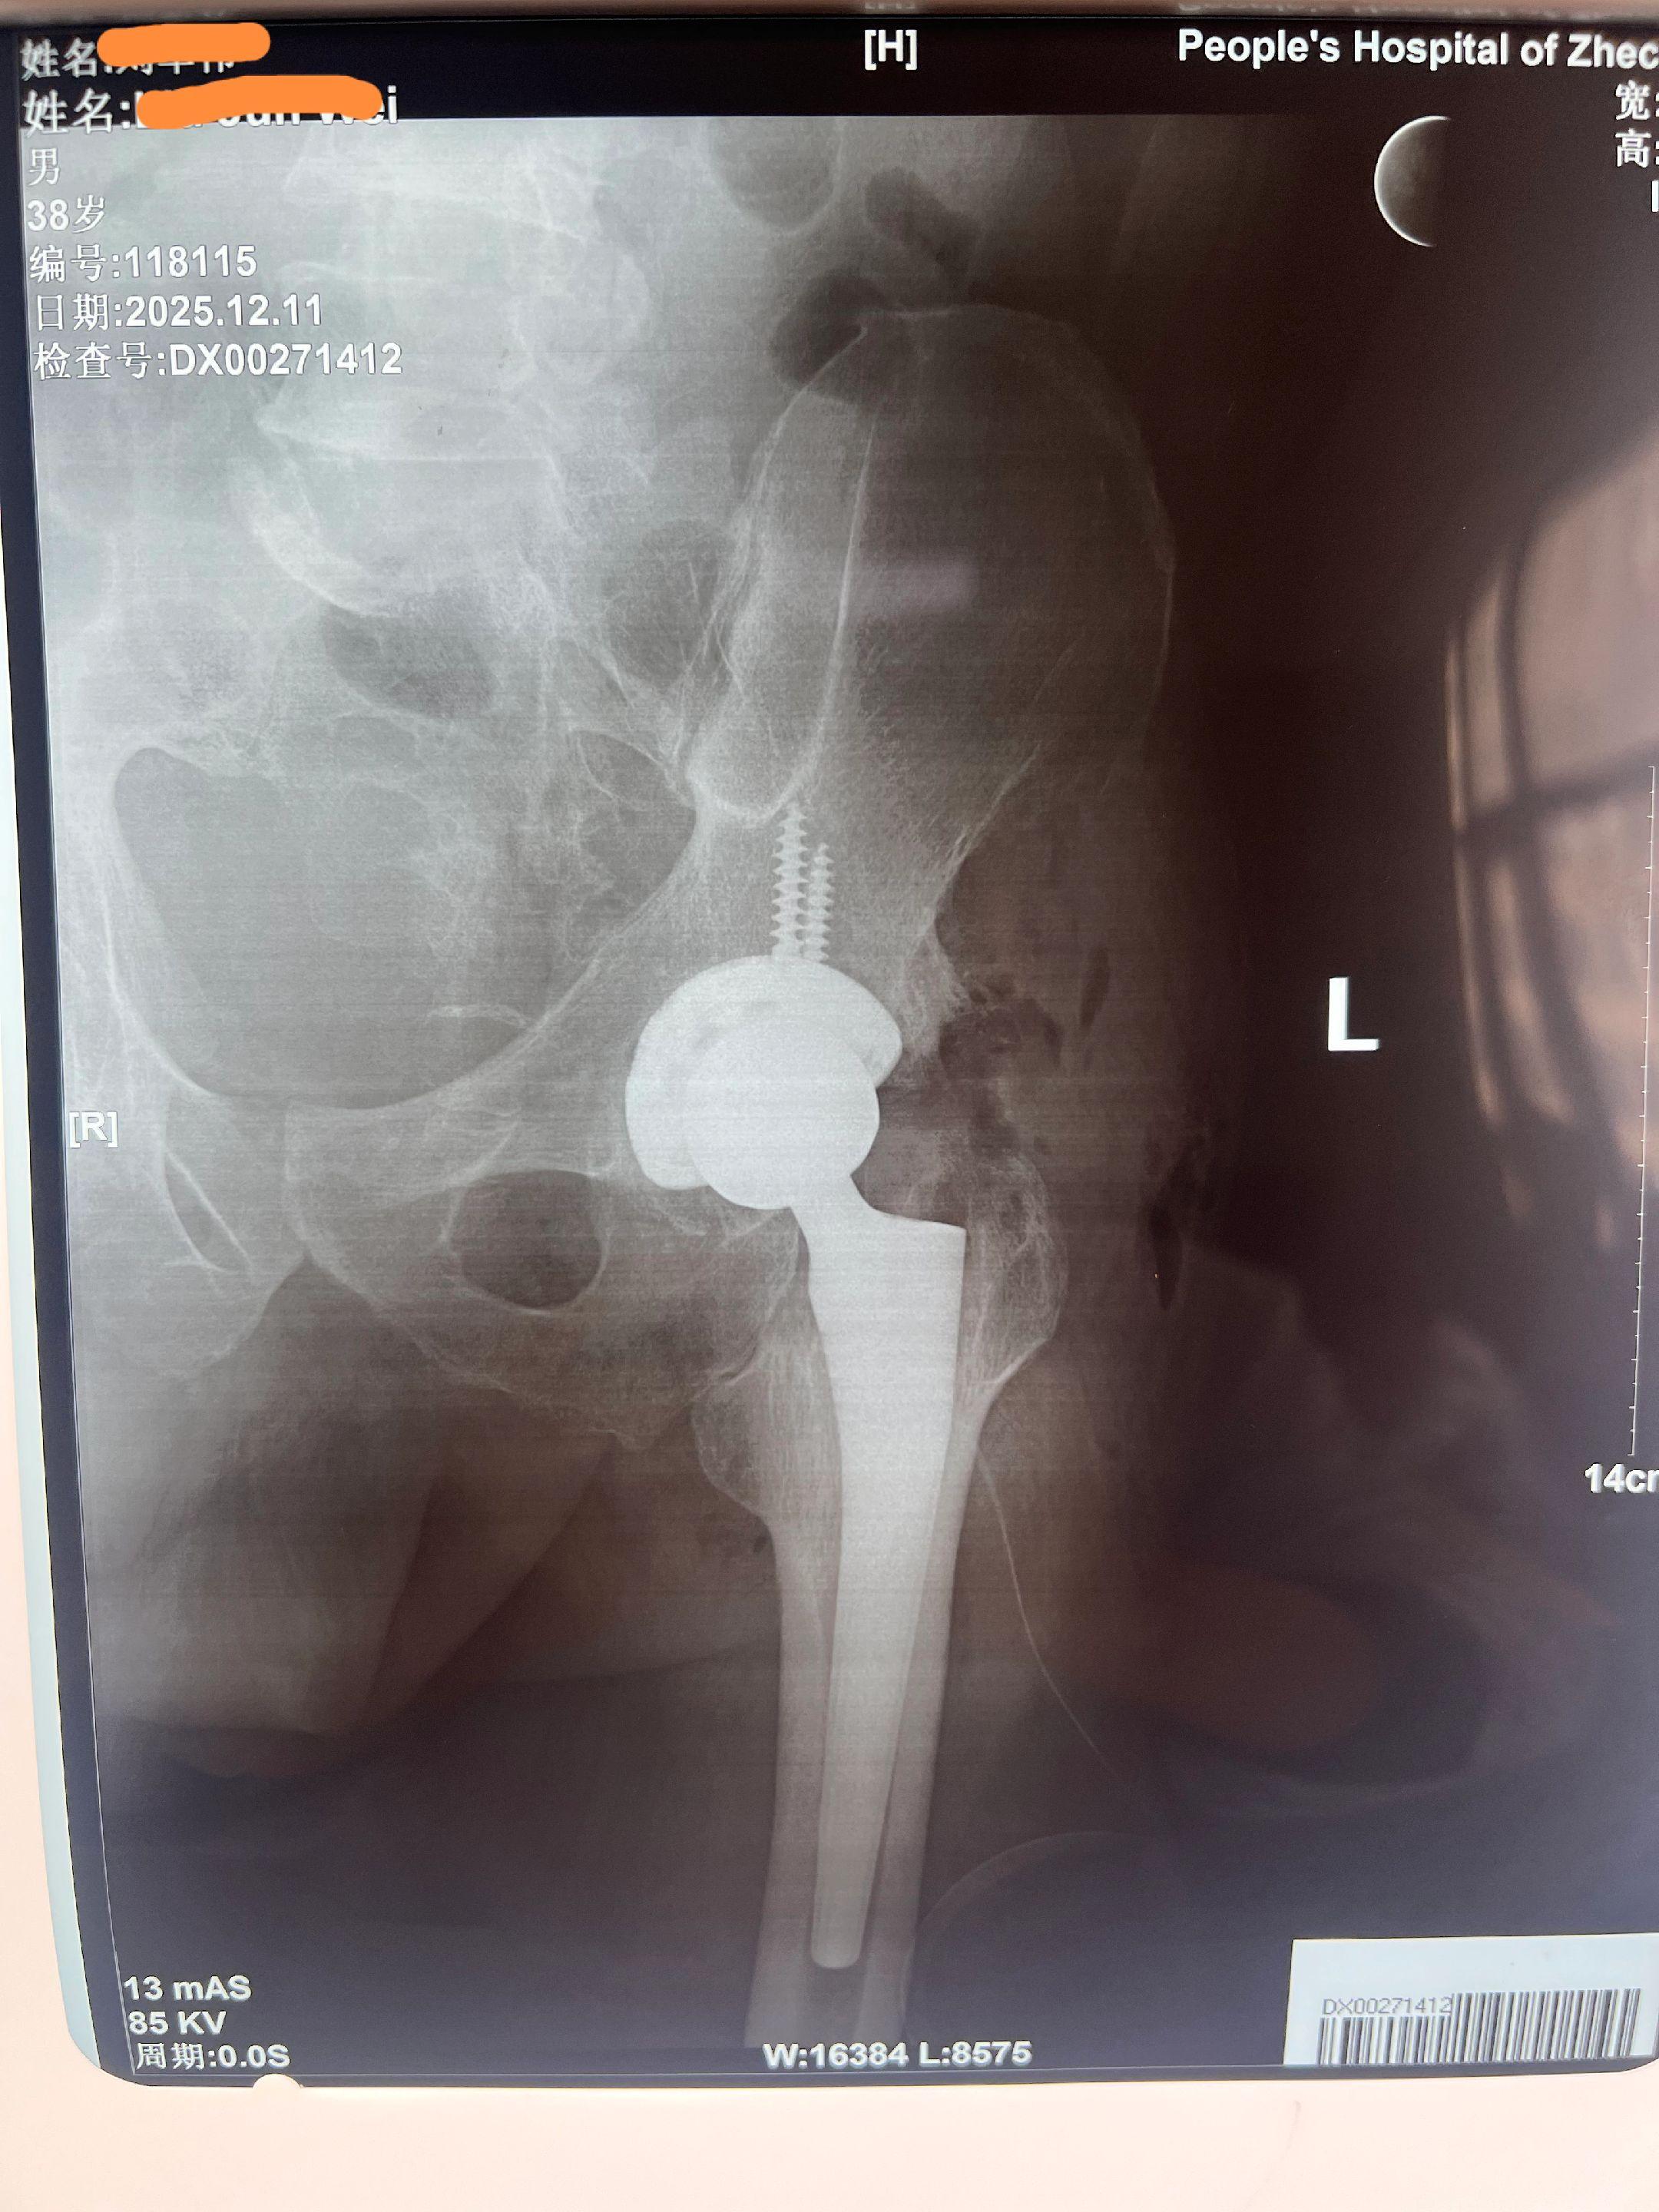

融合髋,髋关节置换。初次THA两个天花板手术之一,融合髋。可怜的孩子,从小髋关节结核,清创手术后髋关节融合,三十年没一点活动度,无法生活,短缩3cm,术后活动自如,恢复等长,希望余生幸福。